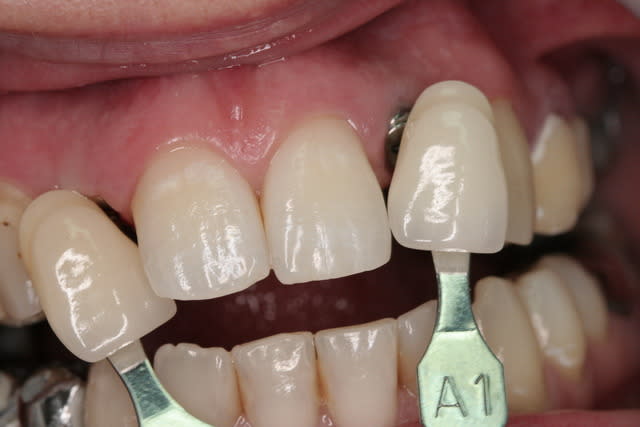

suite bis...

pose de l'implant pas simple en effet pour la 22...la corticale m'a en effet "guidé" beaucoup plus en palatin que ce que j'aurais voulu (cf pano...on à presque l'impression que je suis dans la 21...mais c'est une déformation "optique" les 2 implants ont en effet la même longueur...13mm)

photos de l'empreinte d'étude pour les autres couronnes...photos de la prise de teinte...

je sais qu'il y a une petite différence de hauteur de collet...mais les implants étant pas mal enfouis (les vis de cicat font 3mm) une petite gingivoplastie s'impose pour la 12...

le gain en expansion n'est pas faramineux...mais quand même...

suite des photos après la pose...cette fin de mois...

comme le disait dentiste57...la gestion de ces agénésies est un véritable défi esthétique...